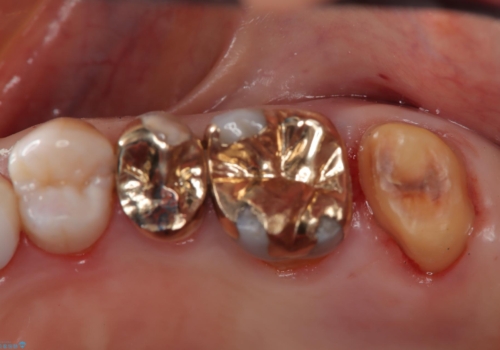

かぶせ物が外れたまま放置 伸びてしまった歯を修復

- 歯のかぶせ物が外れてしまったとのことでご来院された患者様です。左上の奥歯のかぶせ物が外れてしまった後、長期間経過したために、歯が動いて下の歯と手前の歯にぶつかってしまっていました。そのため、まずはレントゲンで内部の神経の位置を慎重に把握しながら、仮歯で歯の位置を調整させていただきました。その後、型どりを行い精密なセラミッククラウンにて治療いたしました。術後の経過は良好です。

今回、歯の位置を調整するのに、矯正治療で利用されるセパレーションゴムにて手前の歯との間を離開しています。これを行わないと、内部の神経が露出するリスクがあります。